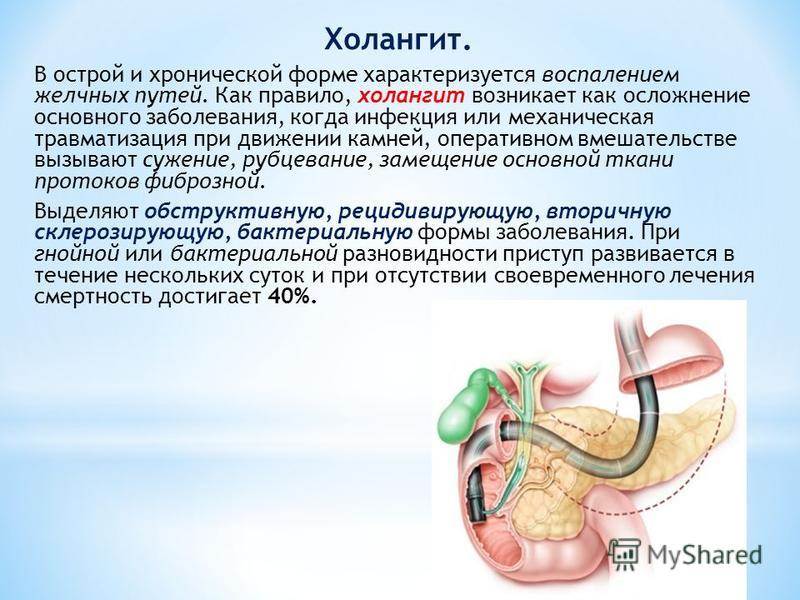

Фотографии и изображения, связанные с симптомами первичного склерозирующего холангита